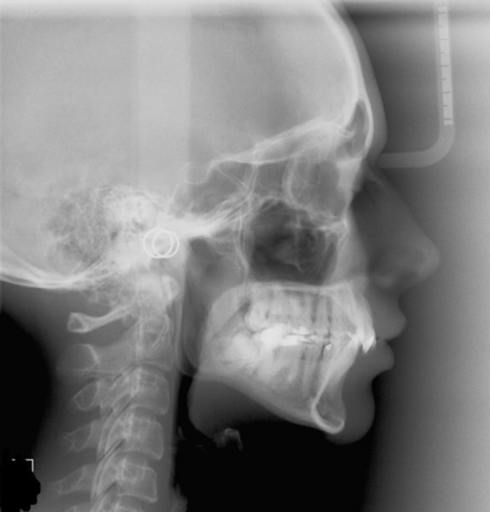

I was wondering if you could take a look aat the x-ray photo to determine whether the left side of my jaw grew bigger than the left. If this is the case, what treatment options are there to correct this problem? Ive heard of dental appliances, are there any others?

It is difficult to diagnose jay irregularities from a two dimensional radiograph. In order to diagnose and treat any abnormality, you would need to have a CT scan completed. This would allow an oral surgeon to diagnose you properly at a consultation visit along with an intra-oral and extra-oral examination. There is not any necessary treatment for jaw asymmetry unless it is causing pain or malocclusion. Most dental appliances are placed during adolescence while you are still developing and the maxilla has not completely fused. After a consultation and diagnosis with an oral surgeon, you may need to see an orthodontist, as many times the two will develop a treatment plan together for the best overall treatment goals and outcome.